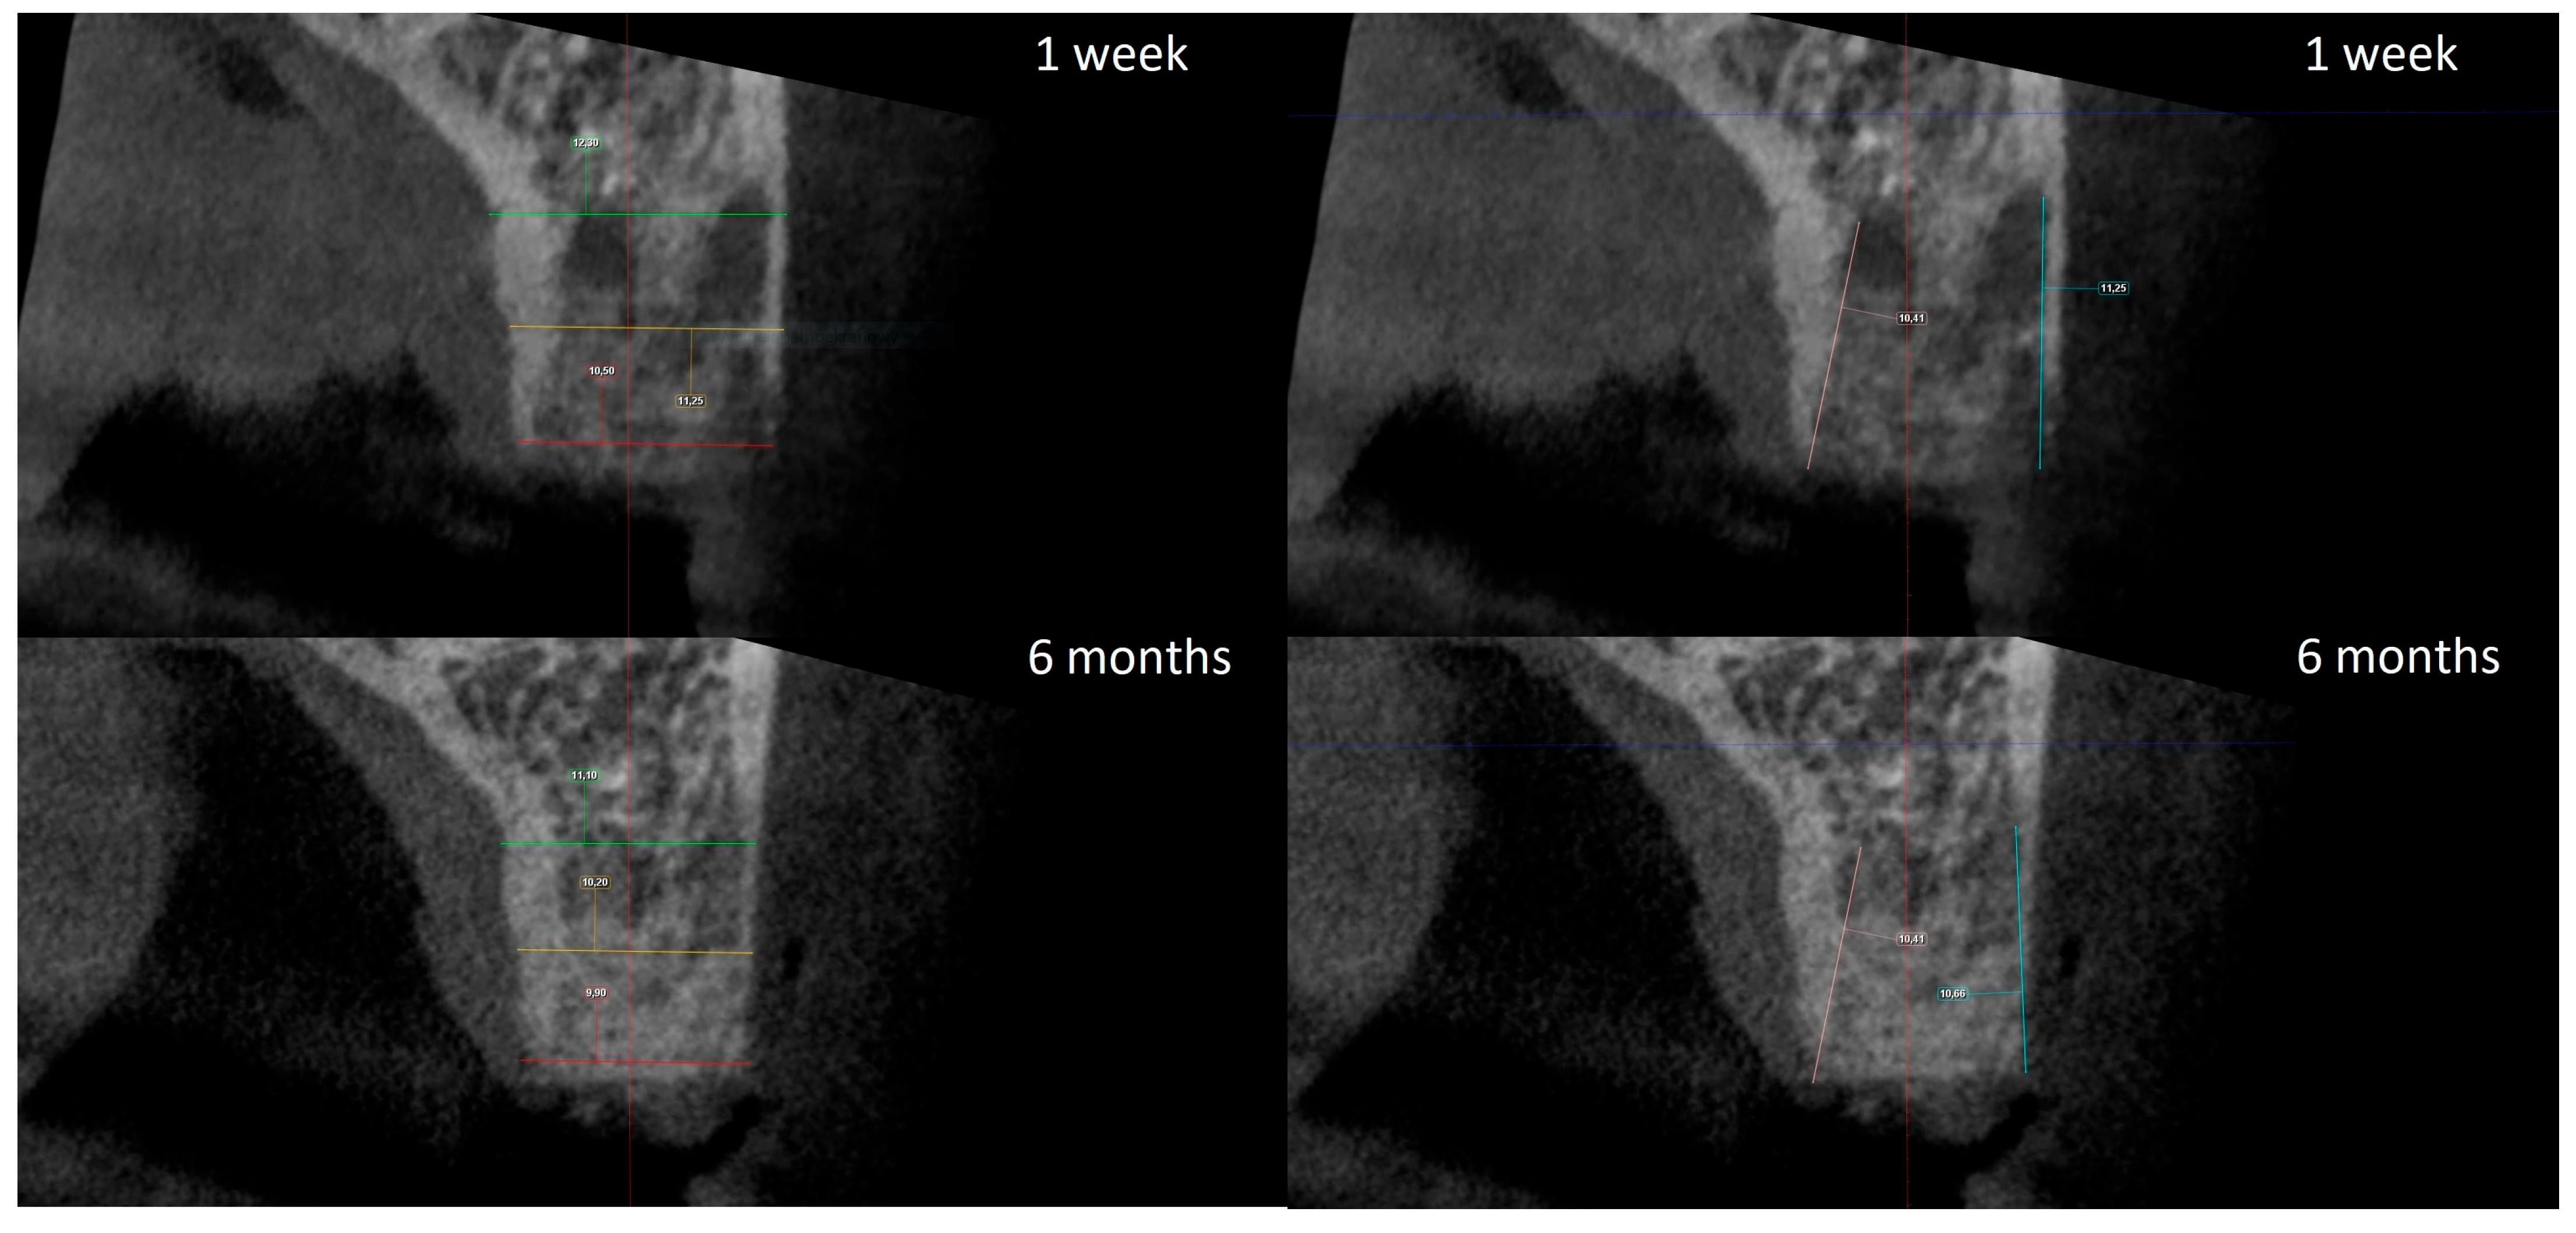

2.4. Radiographic Analysis

The radiographic analysis consisted of alveolar ridge dimension measurements taken 1 week and 6 months post socket preservation surgery. The measurements were made using the Romexis software provided by the Planmeca company. The superimposition of the radiographic images was created automatically by selecting 3 reference points, most often the incisal edges and cusps of adjacent teeth. Afterward, the images were manually corrected (Figure 3). The above-mentioned steps ensured the repeatability of the measurements carried out on sagittal planes, which were oriented in such a manner that the buccal bone plate was parallel to the long axis. The measurements were made in the central part of the alveolus. The distance between the buccal and palatal bony plates was measured at the alveolar crest, the bottom of the alveolus, and midway between these two points (Figure 4A). The height was measured from the bottom of the alveolus to the top of the buccal and palatal bony plates, respectively (Figure 4B).

Figure 4.

(A) Alveolar ridge width measurements: coronally (red line), midpoint (yellow line) and apically (green line); (B) alveolar ridge height measurements: buccally (blue line) and palatally (pink line).

The width and height measurements taken seven days and six months after surgery allowed for the calculation of the alterations of the given dimensions over the healing period. The obtained data are presented in Table 1.

Table 1.

Comparison of alveolar ridge width and height alterations, in millimeters, after 6 months of healing.

The statistical analysis demonstrated no statistically significant differences between groups for all parameters except buccal height alteration. The latter was significantly higher in the xenograft group, with a 1.3 mm average, compared to the 0.5 mm average in the allograft group. For this particular comparison, the statistical significance was estimated to be p = 0.01.